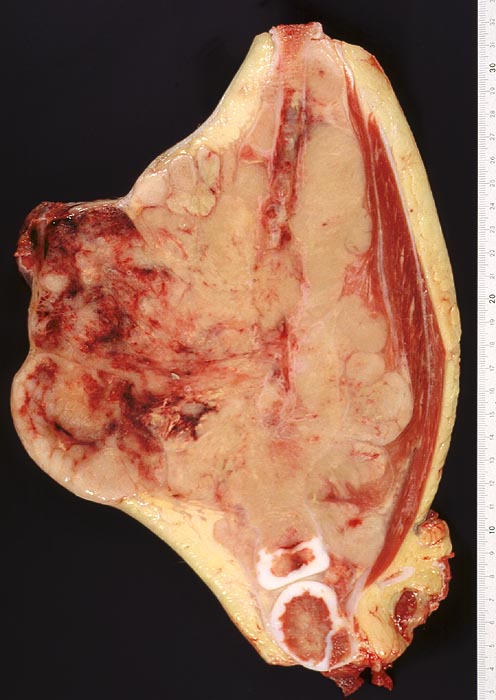

Morphologie:

Die Tumoren sind makroskopisch grauweiss und wachsen destruktiv und infiltrativ. Nekrosen und Einblutungen sind häufig. Histologisch lassen sich solide Rasen monomorpher, kleiner, rundlicher Tumorzellen mit dichtem Chromatin und wenig Zytoplasma nachweisen (sog. small-blue-round cells). Metastasen treten vor allem in der Lunge und in anderen Skelettabschnitten auf. Die Differentialdiagnose klein-blau- und rundzelliger Tumoren im Kindesalter ist breit. Kleinzellige Osteosarkome, Neuroblastome, Lymphome und mesenchymale Chondrosarkome können ein histologisch ähnliches Bild zeigen, speziell in kleinen Biopsien, und müssen mit Hilfe von (molekularen) Zusatzuntersuchungen und unter Einbezug klinischer und radiologischer Befunde voneinander abgegrenzt werden.